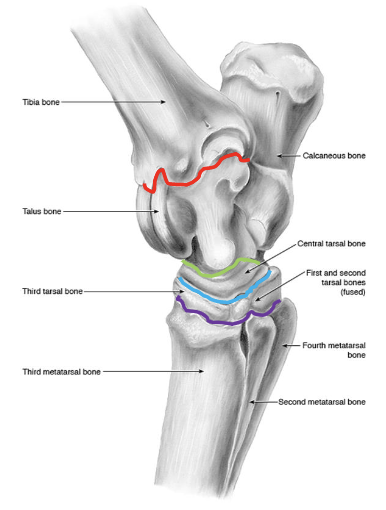

joints of the tarsus

red- tibiotarsal (or tarsocrural)

green- proximal intertarsal

blue- distal intertarsal

purple- tarsometatarsal

which joints of the tarsus communicate w/ e/o

tibiotarsal and proximal intertarsal joints

which tarsal joints are the most common sites of arthritis in horses

distal intertarsal and tarsometatarsal